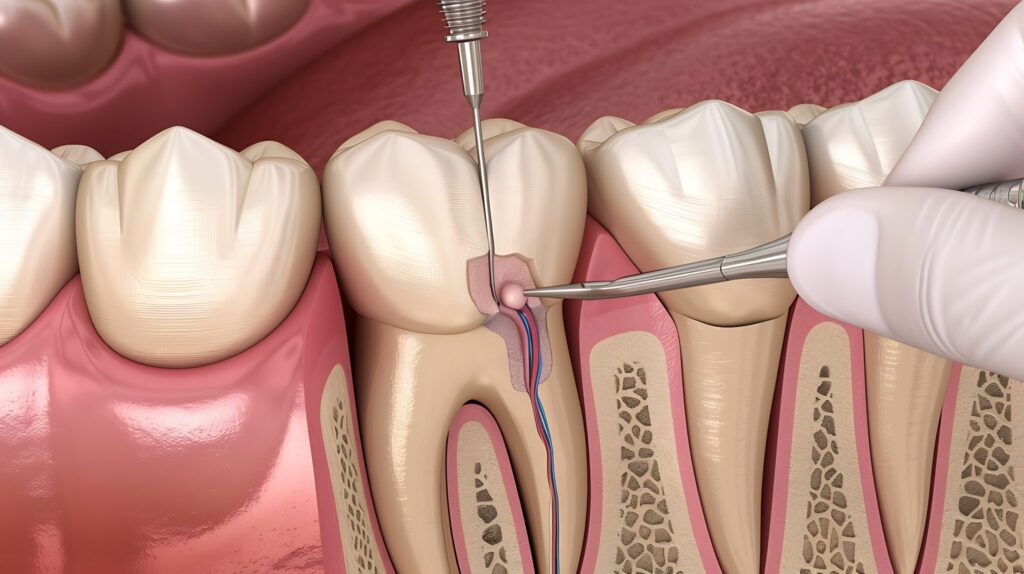

Every tooth has a soft core called the pulp. This contains nerves and blood vessels that help the tooth grow during its early stages. Once a tooth is fully mature, it can survive without the pulp because it continues to be nourished by the surrounding tissues. When decay or an injury reaches this inner chamber, it causes inflammation. This is usually when you start feeling that throbbing sensation that won’t go away with just a salt-water rinse.

Many people are surprised to learn that the process is quite similar to getting a deep filling. The primary goal is to remove the infected tissue, clean the area thoroughly, and seal it to prevent any future issues.

- Initial Assessment: Your dentist will take a look and perhaps a quick digital image to see the extent of the internal damage.

- Comfort First: The area is numbed completely. With the techniques used today, you will likely feel nothing more than a bit of pressure as the work progresses.

- Cleaning and Shaping: Small, precise tools are used to clear out the damaged pulp from the canals.

- Sealing: Once cleaned, the space is filled with a biocompatible material to keep it sterile.